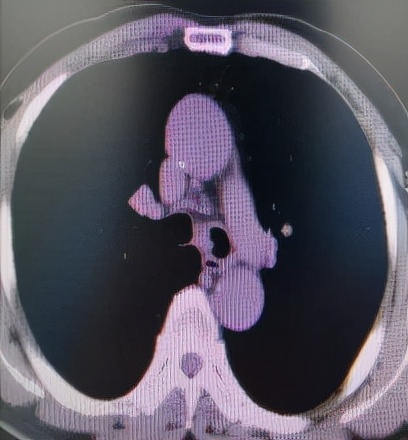

肺 部 C T (削瘤前)

于世寰主任介绍到,患者气管分叉处占位病变面积较大,已累及左、右主支气管,从肺CT影像上判断隆突区病变导致左主支气管狭窄约70-80%左右、右主支气管狭窄约50-60%左右,可操作空间十分有限,支气管镜介入治疗难度较大。隆突区占位病变已累及左右主支气管导致了呼吸困难已不适宜行外科手术治疗,必须通过支气管镜削瘤治疗来解除病人因气道梗阻导致的呼吸困难。支气管镜削瘤治疗与开胸外科手术相比,有痛苦小、创伤小、花费少、可重复性强、并发症少等优点。